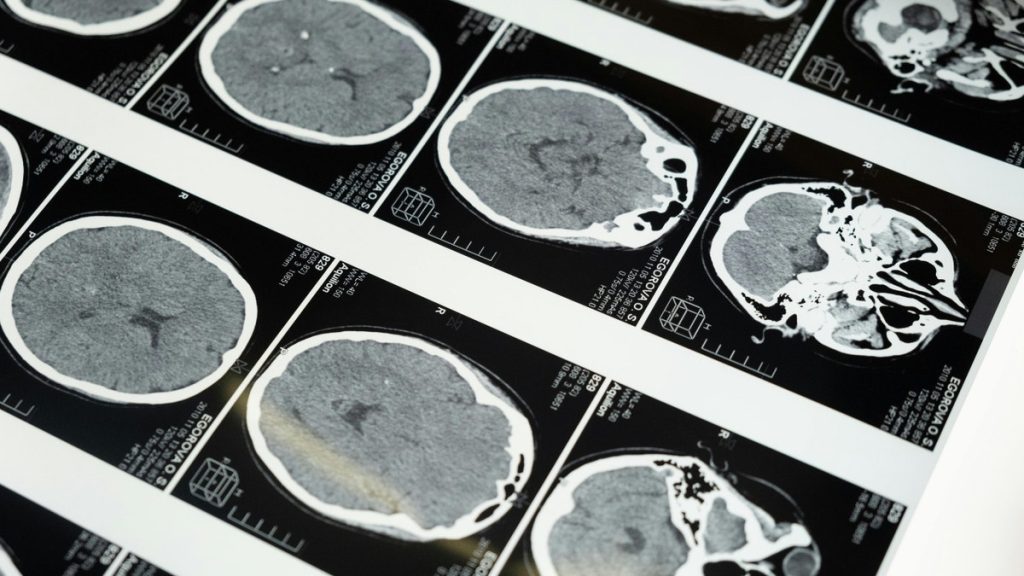

Brain imaging highlights the regions researchers study as companies explore noninvasive ultrasound brain-computer interface technology.(Kurt “CyberGuy” Knutsson)